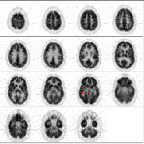

Another type of artifact is caused by normalization errors. A normalization error led to this dark-light pattern in direct (1,3,...) vs. cross (2,4,...) planes. "Normalization" refers to a balancing of the sensitivity or gain among all detector planes. By their geometry, direct planes have higher sensitivity than do cross planes.

Lack of attenuation correction in the left image led to the characteristic "dip" in activity at the center of the skull (particularly in the striatum and thalamus). "Attenuation" refers to a weakening of the gamma-ray signal from an imaged site due to the presence of other structures. Bone causes higher attenuation than does soft tissue. Attenuation correction compensates for this weakening of the signal.